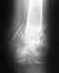

Перелом локтевой кости левой руки со смещением(снимки прилагаю).